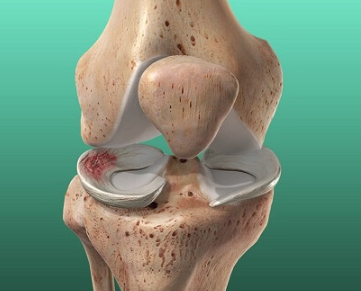

**무릎 연골 찢어짐 치료**는 손상의 위치, 크기, 증상 정도에 따라 접근 방법이 달라집니다. 병원에서는 MRI 등의 영상검사를 통해 상태를 정확히 파악할 수 있으며, 다양한 보존적 또는 수술적 치료법이 존재합니다.

보존적 치료에도 증상이 계속되거나 기능 장애가 심한 경우, 관절 내시경 수술을 통해 손상 부위를 다듬거나 이식하는 방법도 고려될 수 있습니다. 다만, 수술 여부는 전문가의 판단이 필요합니다.